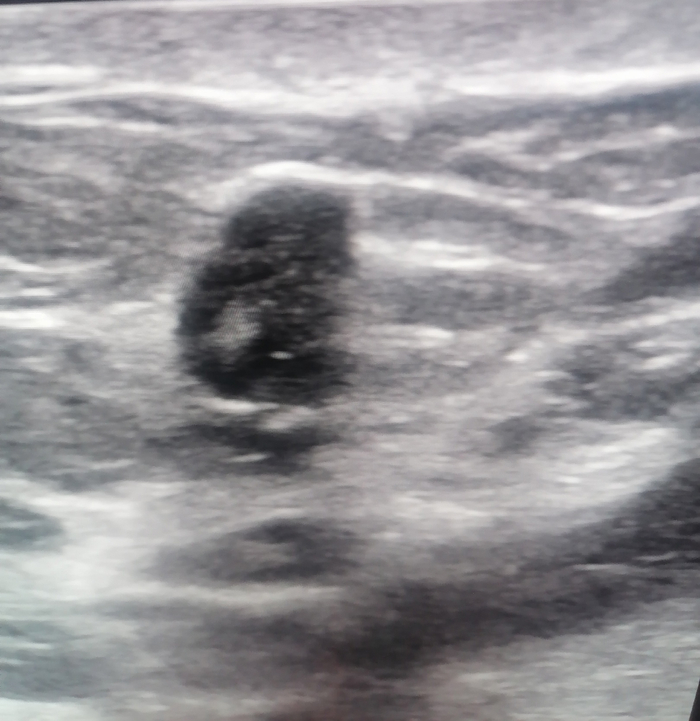

Для сравнения, другая молочная железа у той же пациентки:

Тоже, скорее всего рак (да, так тоже бывает), но с куда более классическими признаками.

Да, в учебниках пишут, что в некотором проценте случаев (не нашел конкретных цифр, если обладаете статистикой - пишите в комментариях), рак может выглядеть как образование повышенной эхогенности. Но одно дело прочитать в учебнике, а другое - встретить в практике.